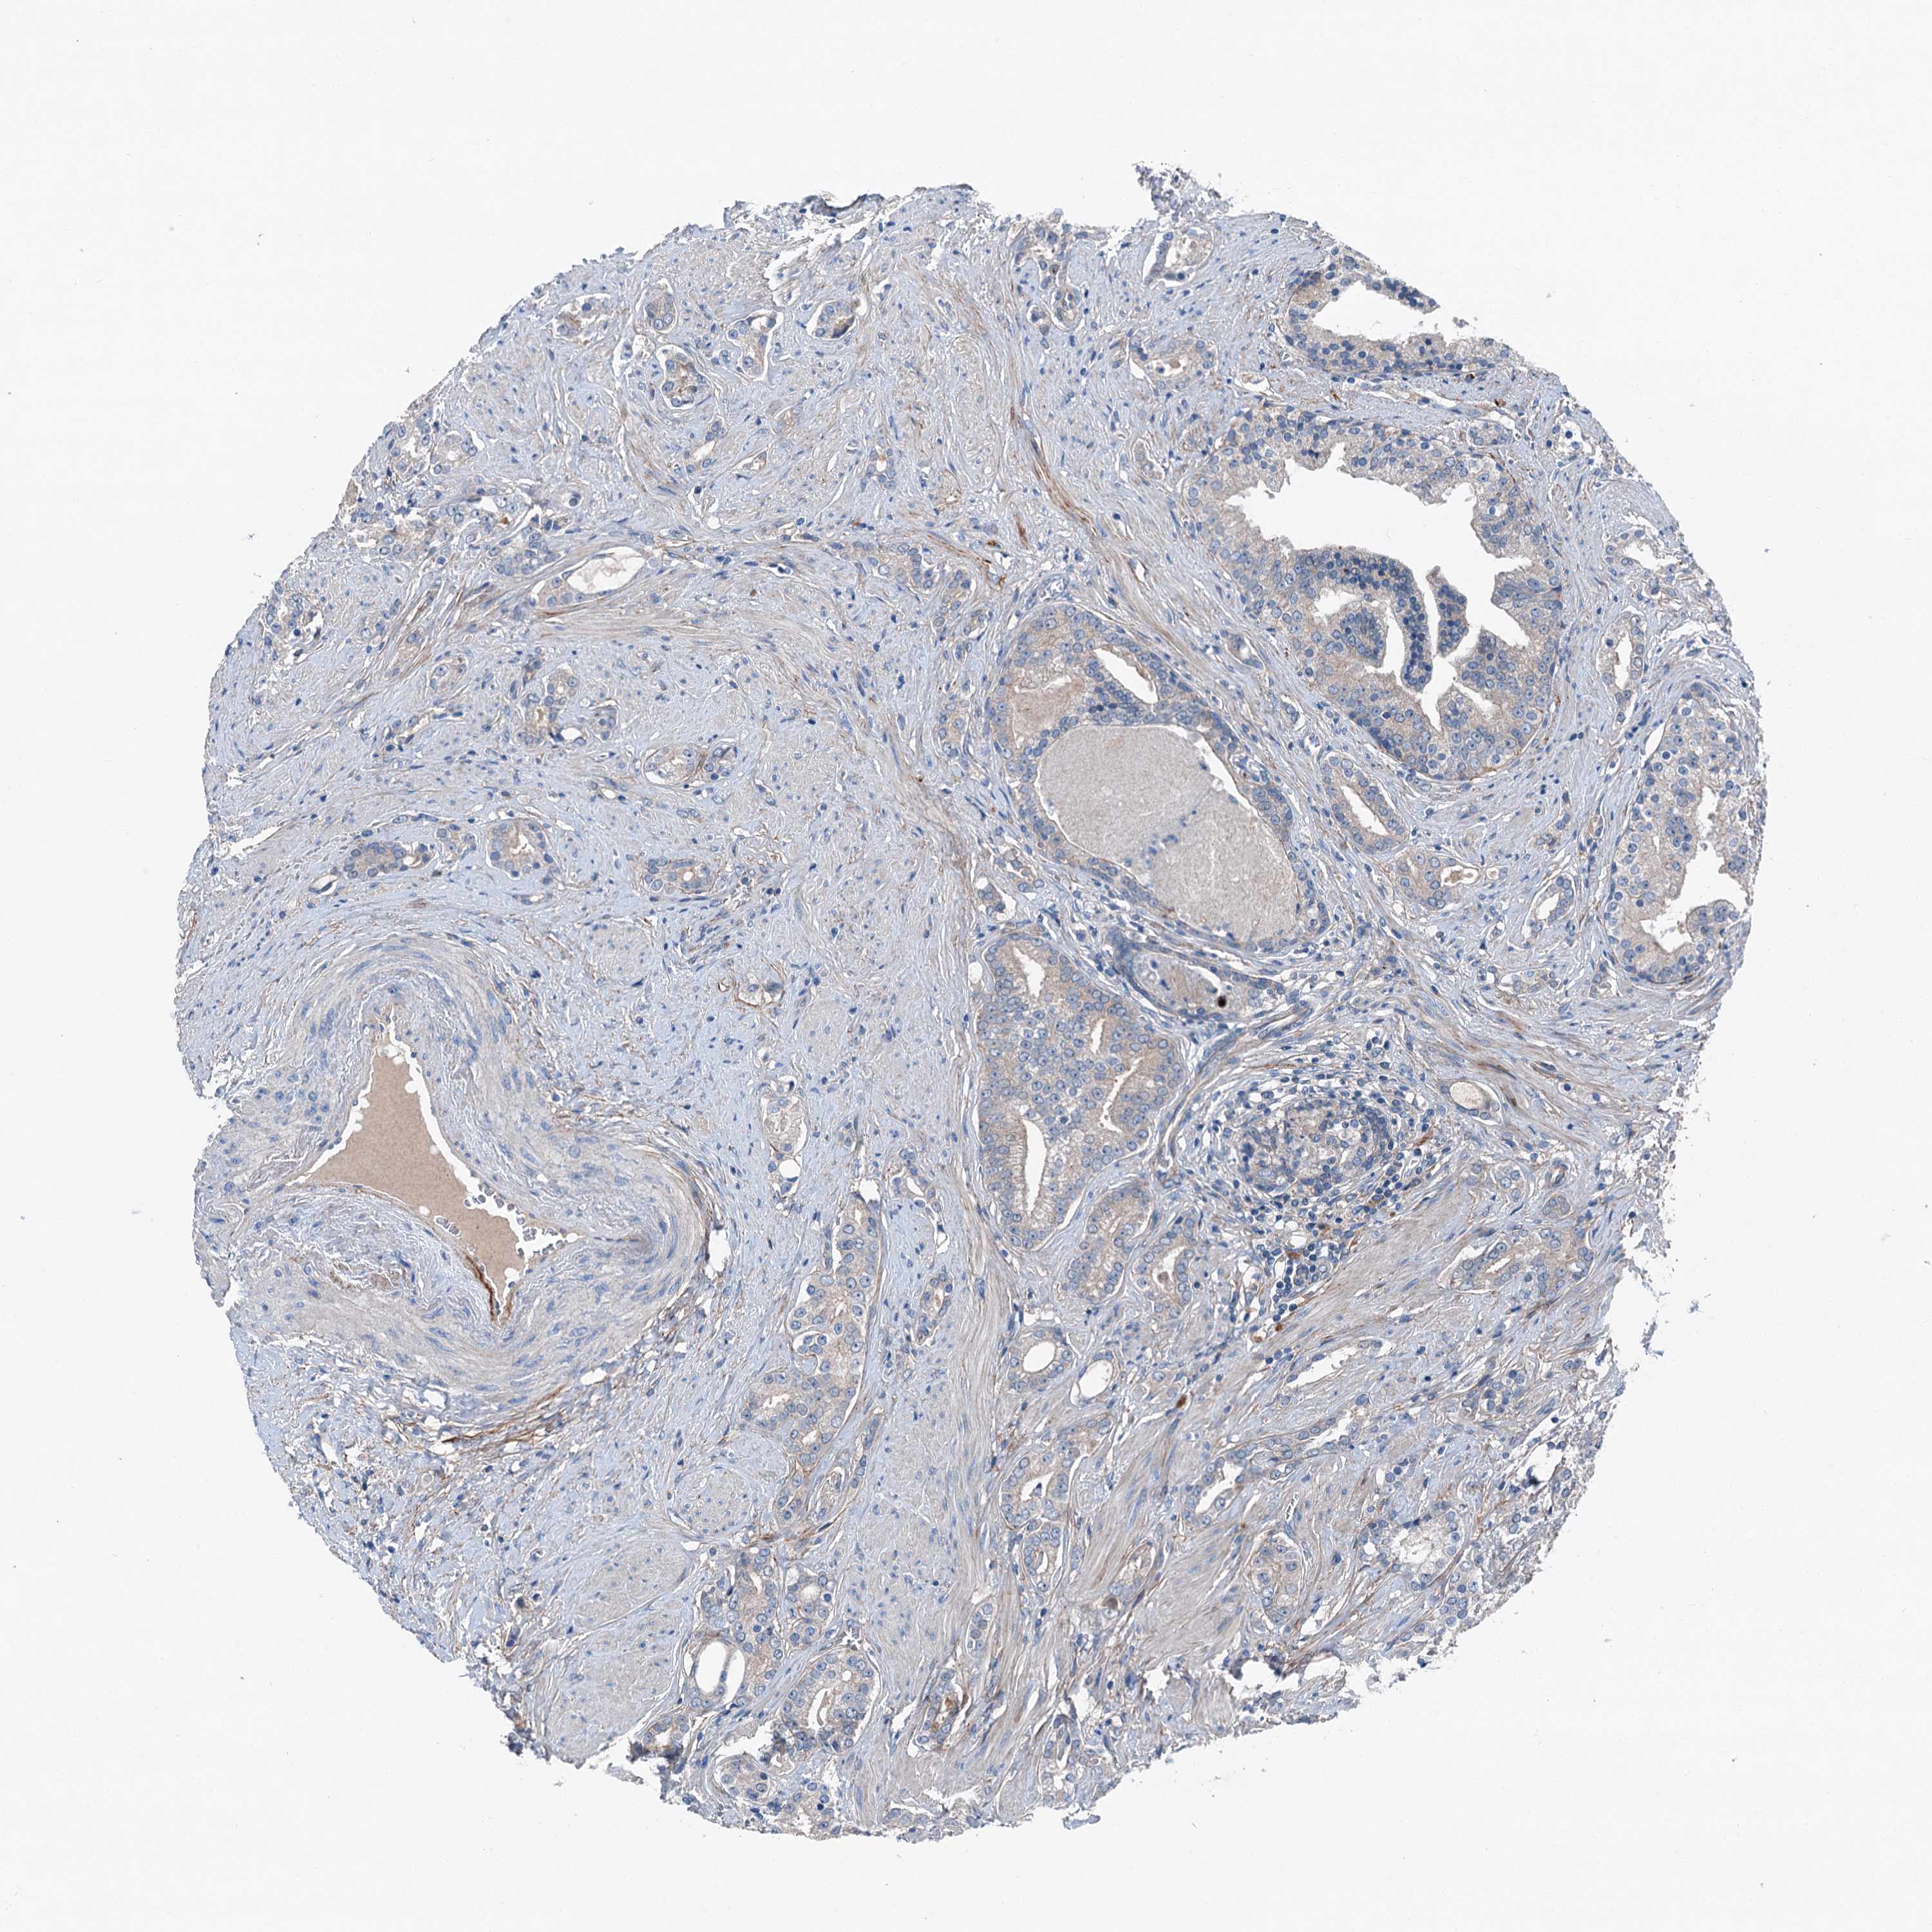

PROSTATE CANCER - Protein expressioni

A mouse-over function shows sample information and annotation data. Click on an image to view it in a full screen mode. Samples can be filtered based on level of antibody staining by selecting one or several of the following categories: high, medium, low and not detected. The assay and annotation is described here.

Antibody stainingi

Antibody staining in the annotated cell types in the current human tissue is reported as not detected, low, medium, or high, based on conventional immunohistochemistry profiling in selected tissues. This score is based on the combination of the staining intensity and fraction of stained cells.

Each image is clickable and will lead to virtual microscopy that enables deeper exploration of all samples and also displays staining intensity scores, fraction scores and subcellular localization as well as patient and tissue information for each sample.

Antibody HPA041015

Staining

High

Medium

Low

Not detected

Intensity

Strong

Moderate

Weak

Negative

Quantity

>75%

75%-25%

<25%

None

Location

Nuclear

Cytoplasmic/membranous

Cytoplasmic/membranous,nuclear

Adenocarcinoma, High grade

Adenocarcinoma, Low grade